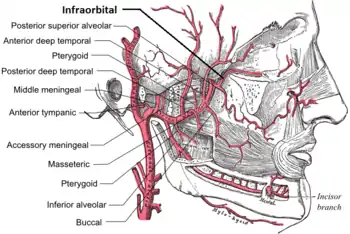

Plan of branches of internal maxillary artery. (Infraorbital at far right.) | |